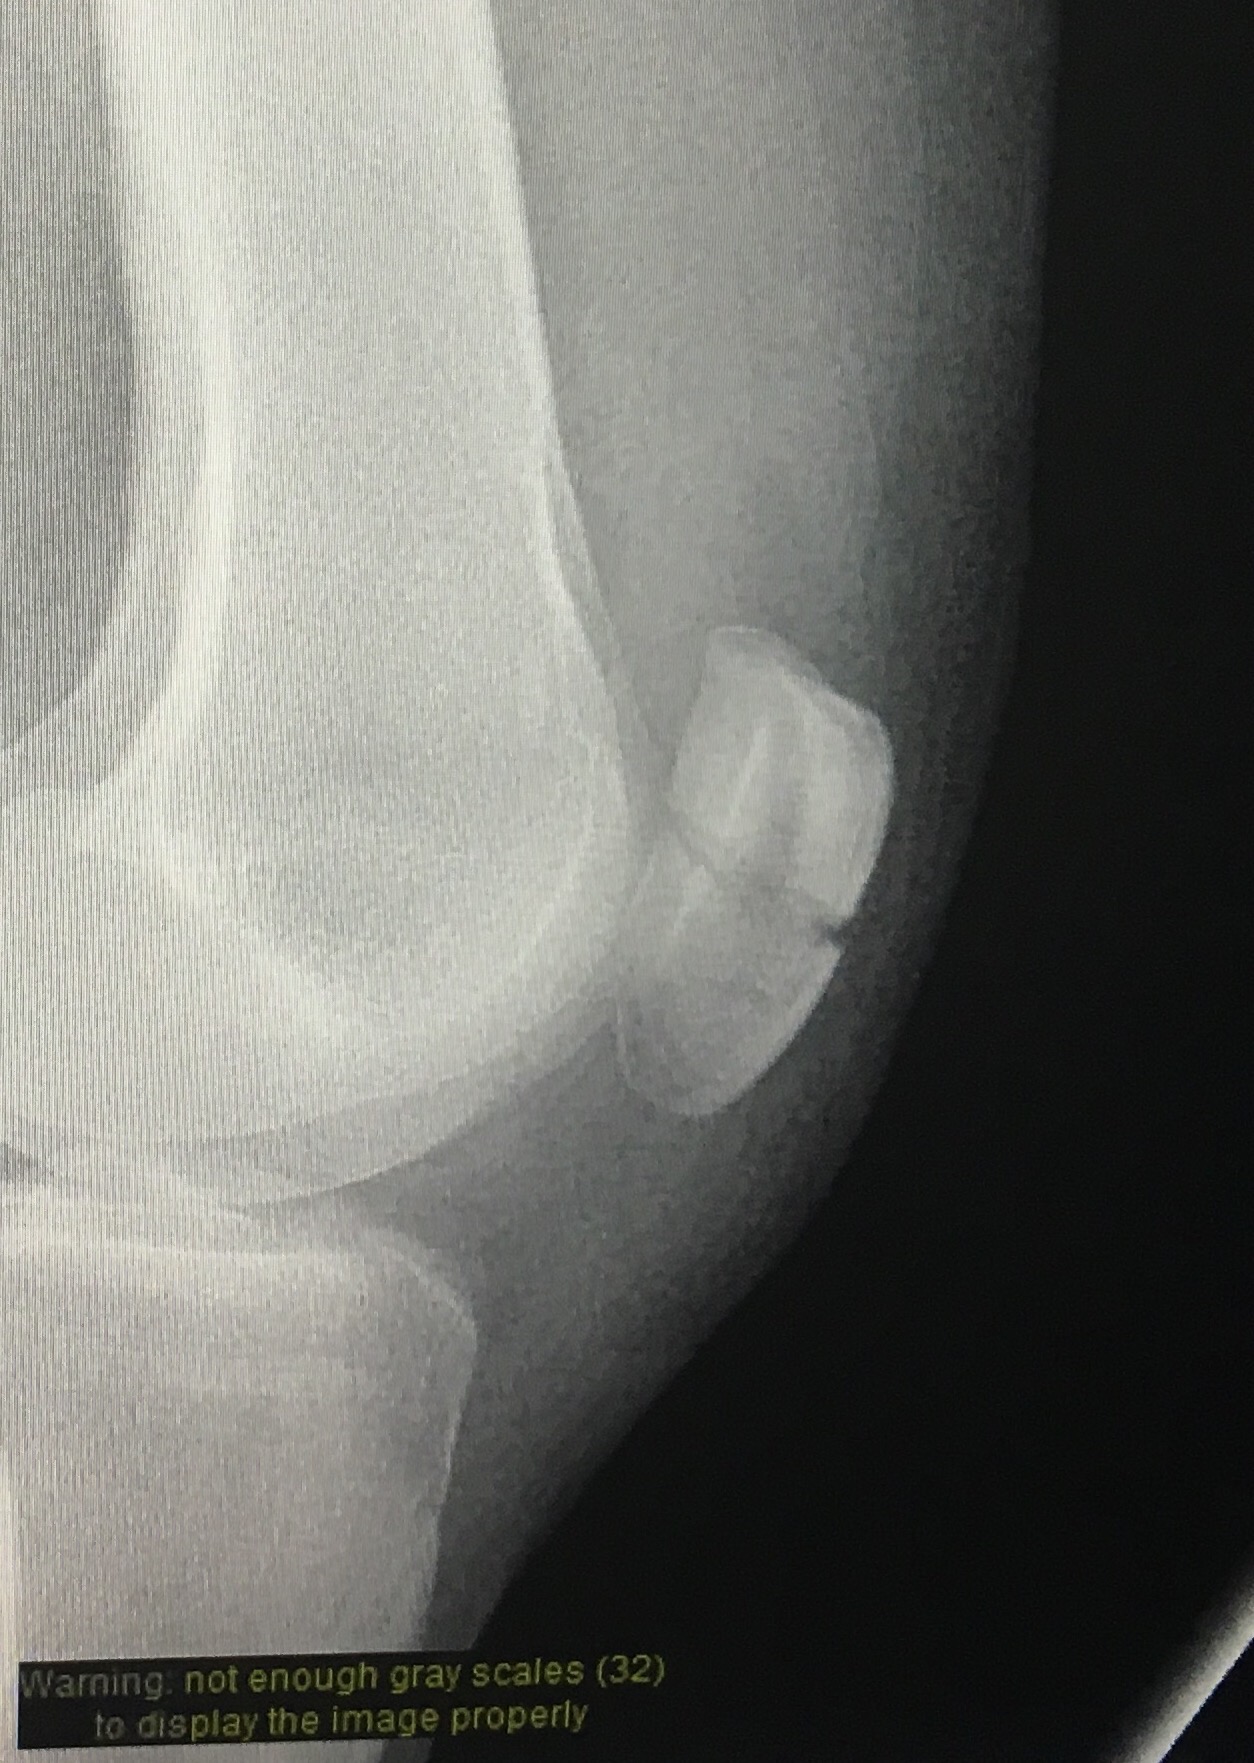

Upon painful reflection, I have three main problems: (1) despite a recent change in job I am no less of a freak who hides from life in her work than I was 3 weeks ago; (2) my patella is cracked completely in half; and (3) I should really shave my legs more often.